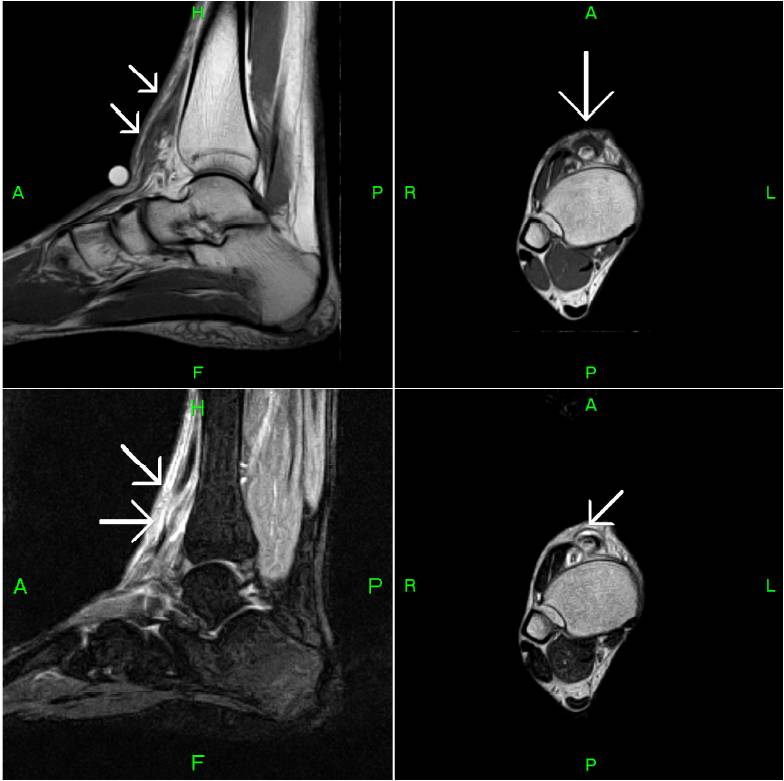

MRI MusculoSkeletal Section Anterior compartment

MRI findings in crural compartment syndrome a case series SpringerLink Anterior Compartment Syndrome Mri Infrared spectroscopy and magnetic resonance imaging (mri) may have a future role in diagnosing compartment syndrome; While some cases of myositis can develop into acute compartment syndrome (acs), the most common cause of acs are tibial. It is a painful condition caused by increased. However, their role in current management is not established. Chronic exertional compartment syndrome has characteristic mri. Anterior Compartment Syndrome Mri.